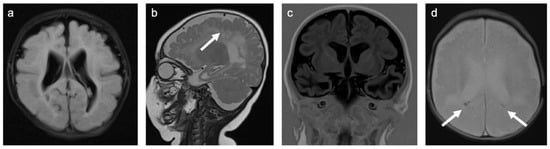

Group 6 consisted of twelve patients. Five patients were diagnosed with congenital cytomegalovirus infections, five with central nervous system manifestations of mycoplasma infection, and two with a central nervous system manifestation of a TORCH infection. A representative case is shown in Figure 7. In total, 33% of patients were female and the mean age was 5.1 years (min 0.4 years; max 14.2 years). A total of 83% of patients were examined with contrast-enhanced MRI. Of those examinations, 20% showed enhancing lesions. WMSAs in this group of patients were localized supratentorial in all but one patient who showed additional infratentorial lesions. A total of 83% of patients had multifocal WMSAs.

Figure 7. Representative case “Infectious white matter damage”: congenital cytomegalovirus infection. FLAIR (a), T2W (b), Turbo inversion recovery (TIR; (c)), and T2*W (d) sequences. Four-month-old girl with a history of congenital cytomegalovirus infection. MRI shows microcephaly with polymicrogyria ((b); white arrow), bilateral ventriculomegaly (ad), global thinning of the cerebral mantle, especially temporal (b,c), bilateral white matter signal abnormalities in the frontal and parieto-occipital regions (a), and punctuate periventricular calcifications ((d); white arrows).